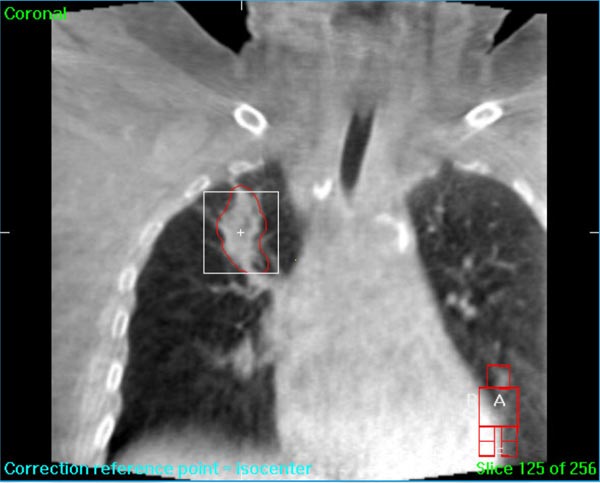

We understand that a cancer diagnosis can be scary, which is why Florida Center For Prostate Care is dedicated to compassionate care and state-of-the-art technology. Florida Center For Prostate Care uses the Elekta Synergy® machine, a digital accelerator for advanced image-guided radiation therapy (IGRT). It is the only all-digital treatment device in the world. This allows your doctor to view your tumor in real-time at the time of your treatment.

The 3-D high-quality images taken at the time of your treatment can be studied against your previous CT scans precisely and promptly to ensure that the doctors are treating your tumor as accurately as possible while greatly limiting any exposure to healthy tissue in the area.

Elekta Synergy® provides unparalleled clinical assurance to more aggressively treat tumors while keeping damage to surrounding healthy tissues to a minimum. Elekta Synergy®‘s precision accuracy reduces or eliminates the use of markers because clinicians can view soft tissue using Elekta Synergy®‘s VolumeViewTM. The low-dose imaging proficiency helps minimize the side effects of radiation therapy by decreasing the margins previously set to account for the unpredictability of target location, movement, and dimensions.